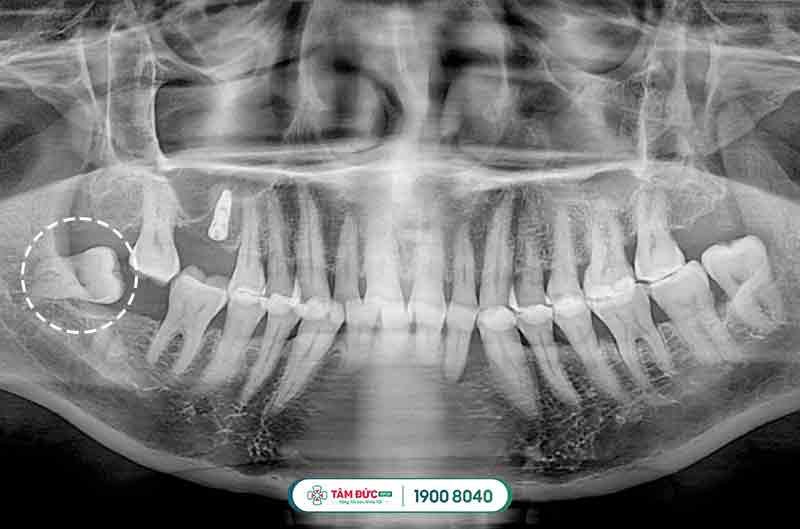

2.3.1. Tiến hành chụp phim X-quang

Chụp x-quang chiếc răng khôn mọc lệch để xác định vị trí, cũng như hướng mọc răng như thế nào rồi đưa ra phương pháp nhổ bỏ thích hợp nhất.